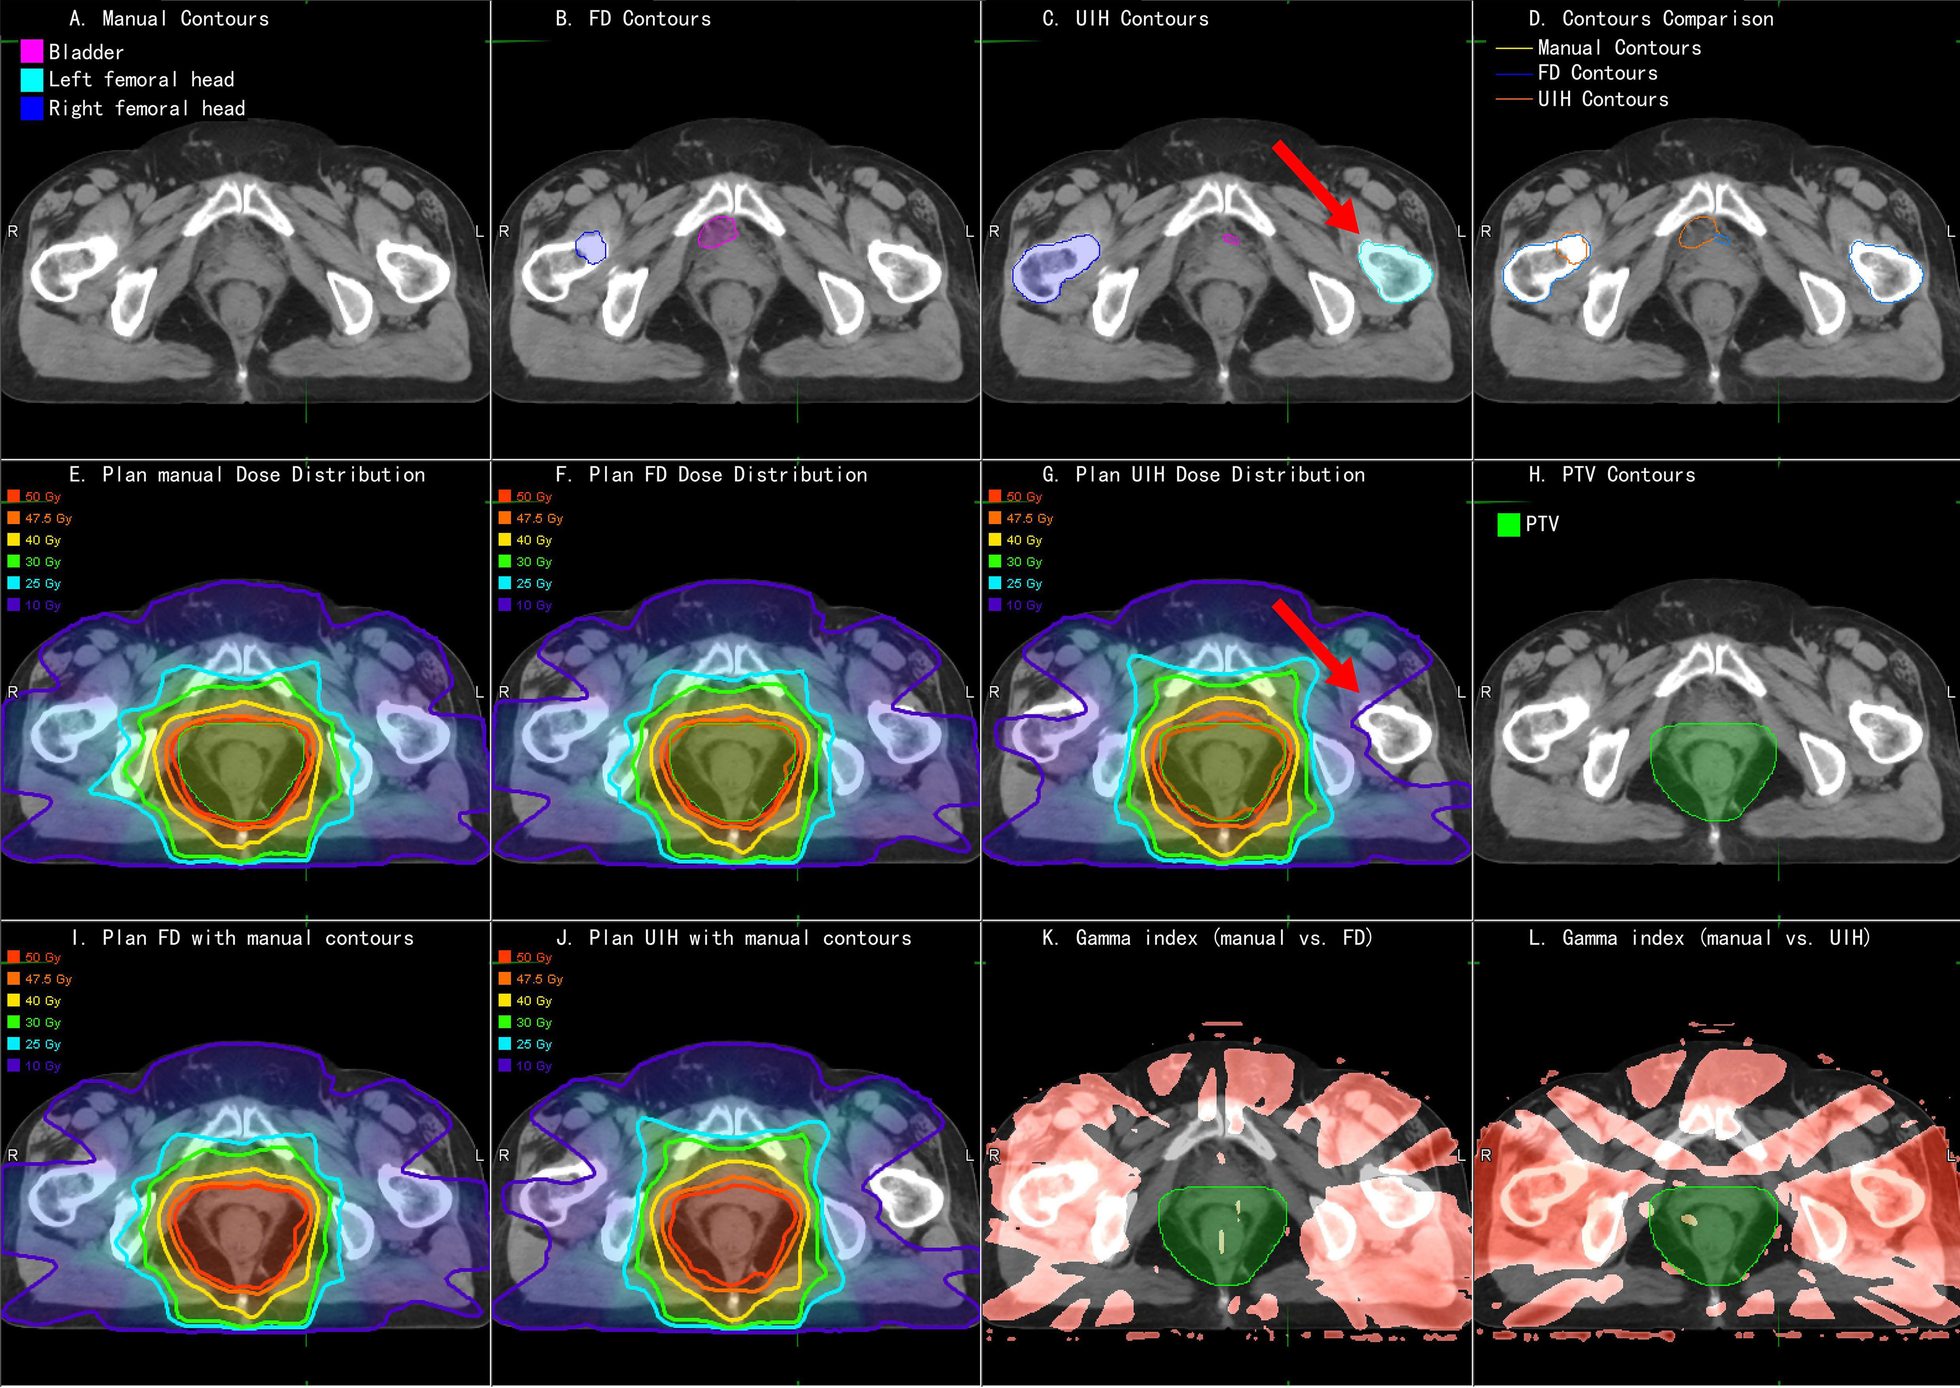

Fig. 4

An example of rectal cancer patient. a Manual OARs; b FD OARs; c UIH OARs; d Contour comparison; e Plan_Manual dose distribution; f Plan_FD dose distribution; g Plan_UIH dose distribution; h PTV contour; i Plan_FD with manual OARs; j Plan_UIH with manual OARs; k 3D Gamma analysis of Plan_FD; red color represents gamma index > 1; l 3D Gamma analysis of Plan_UIH, red color represents gamma index > 1